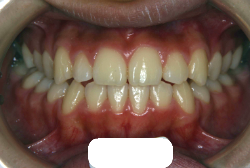

叢生(そうせい)

凸凹な歯並びのことを叢生といいます。矯正歯科に来院する患者様の主訴の中で、最も多いのが「配列の凸凹を真っ直ぐにしたい」というものです。歯の大きさと顎の大きさの調和がとれていないことが原因です。

凸凹を主体としたケースの場合、当院の平均治療期間は18ヶ月ですので、このケースは少し長めに経過しました。理由の一つは凸凹の程度がかなり重症だったと言うことですが、もう一つは、右下第2大臼歯が45度くらい前傾していたため、それを整直化させるために時間を要したと考えています。いずれにしても最終結果は大変よい状態と思います。

治療前は並びが乱れて見た目が悪いというのはもちろん問題ですが、歯科医学的に一番困るのは噛み合わせが悪いという点です。上下の犬歯(3番目の歯)は、上下的に離れた位置にあるため接触することができません。つまり歯としては存在していても、歯としては機能していないということです。